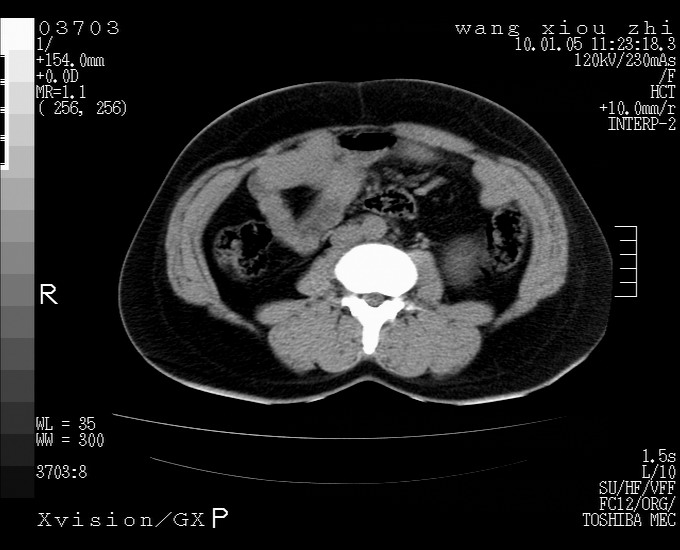

标题: CT23996:f,40.B超提示肿物。 [打印本页]

标题: CT23996:f,40.B超提示肿物。

左肾体积增大!下极见一密度略高团状软组织影!肾周结构组织未见明显异常!考虑左肾占位!建议增强!病史?

左肾占位性病变,建议增强。

实性影 肾癌

左肾占位性病变,考虑肾癌,建议增强 。

左肾占位,肾门及腹膜后淋巴结肿大,考虑透明细胞癌可能性大,建议增强

左肾体积增大,内见肿块影,考虑占位,建议增强。

左肾占位考虑肾癌

左肾占位性病变,不排除肾癌可能;建议行进一步检查。